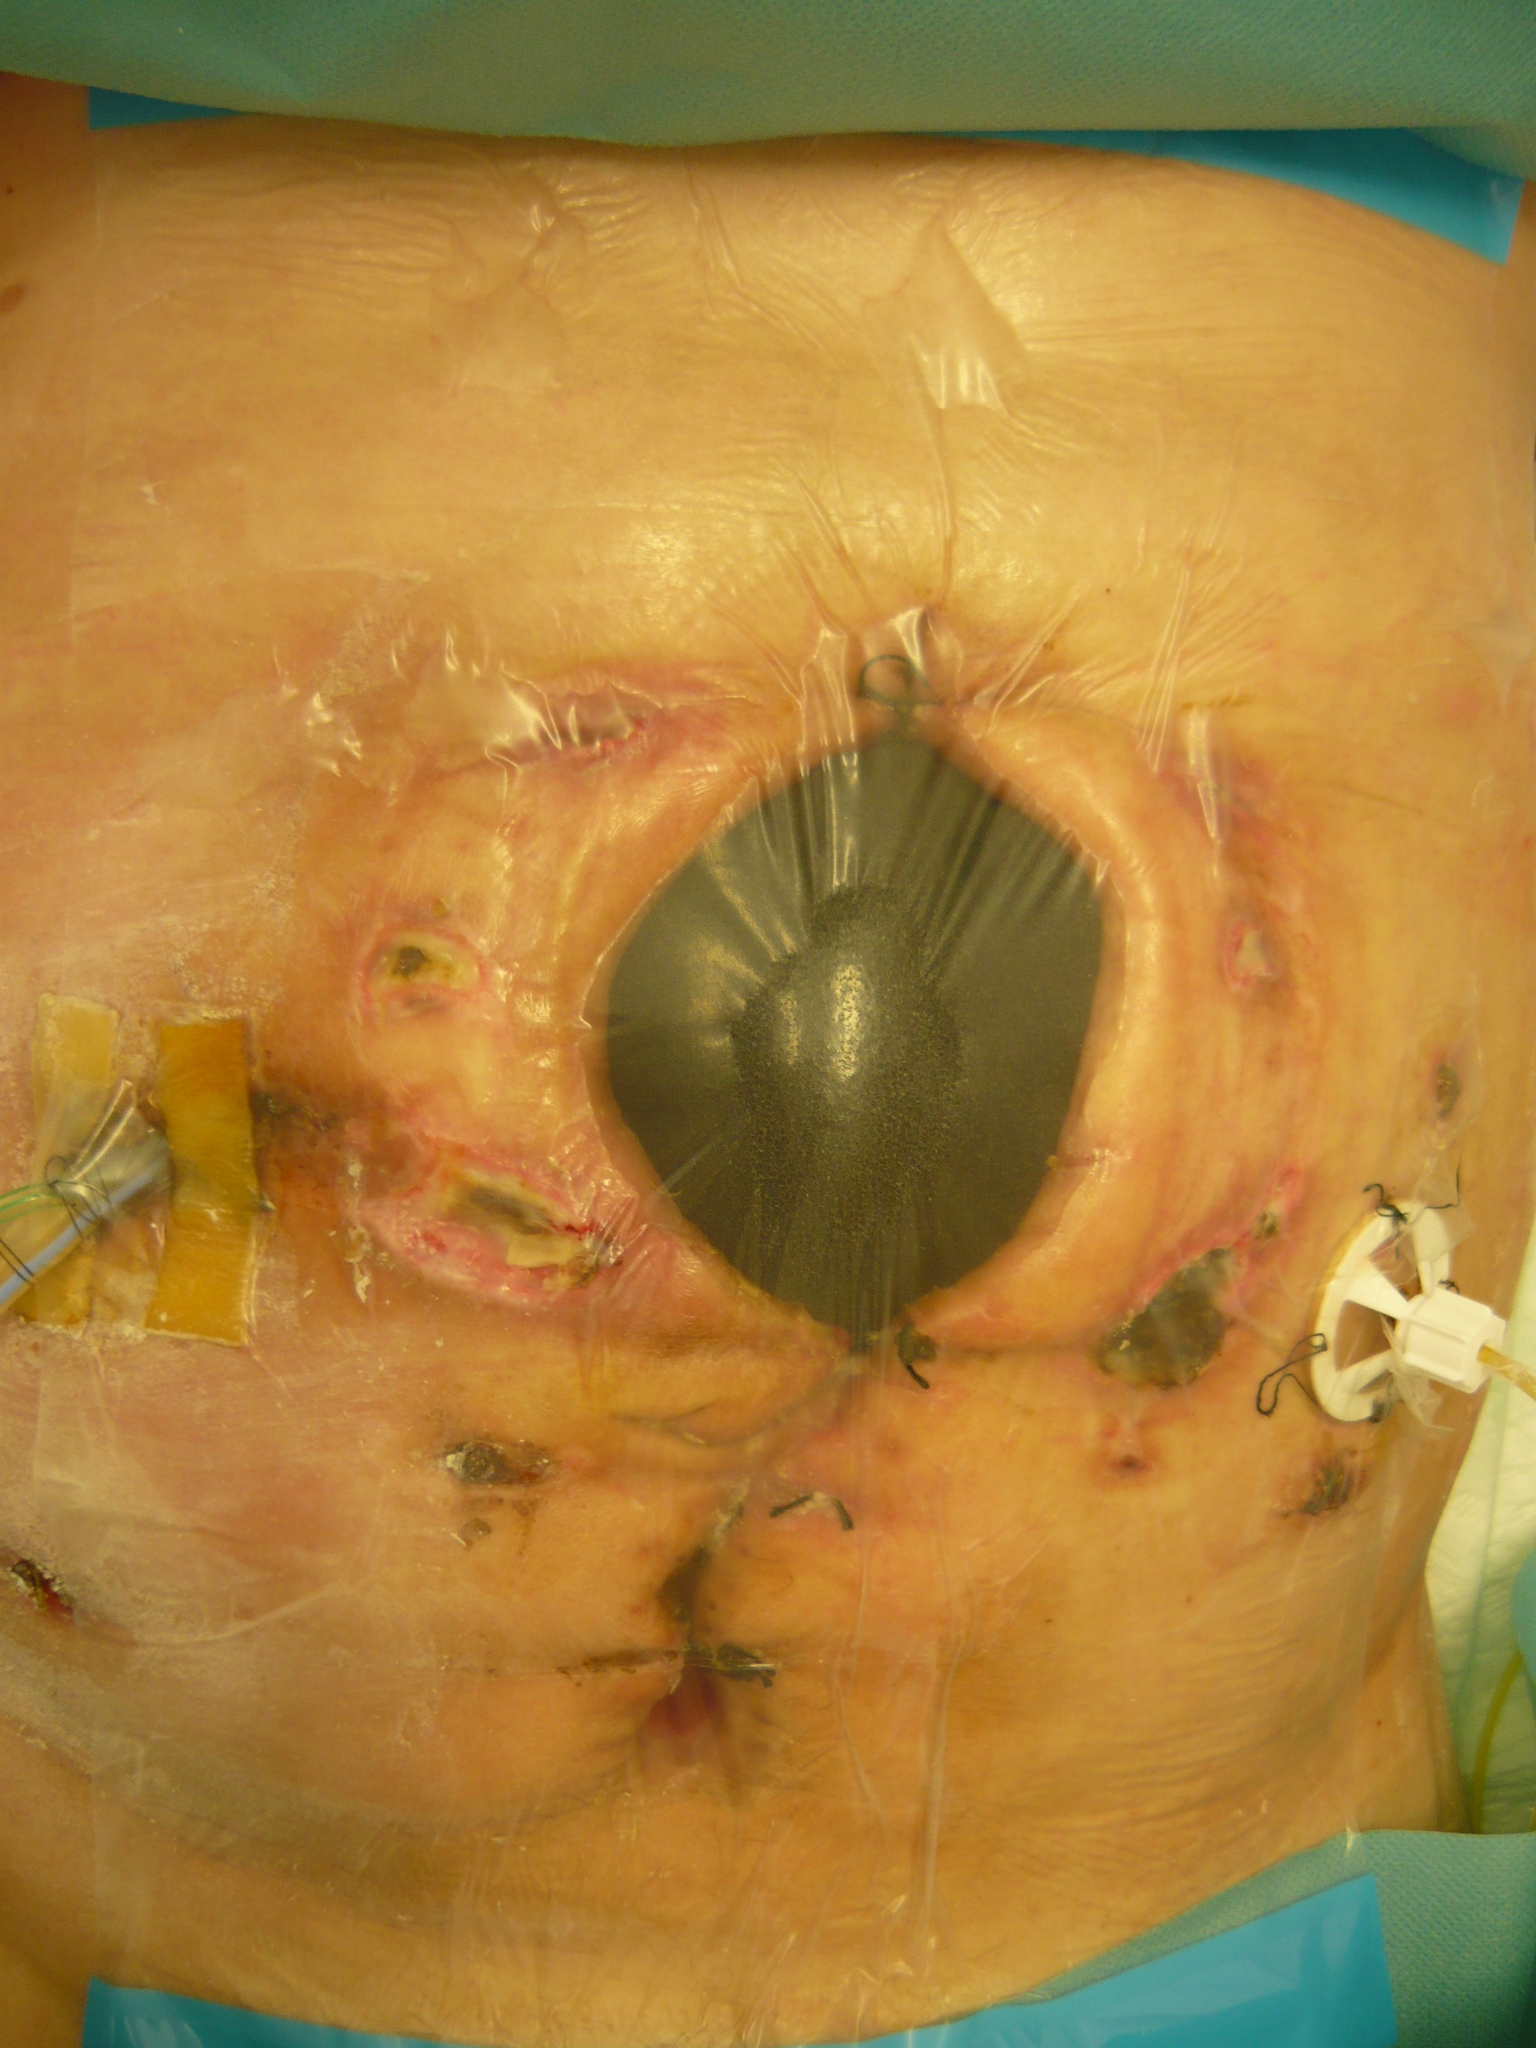

14. 1. 2010. Laparostómia i jej okolie naďalej monitorované. Po desiatich dňoch používania klasickej terapie (pravidelné preplachy antiseptickým roztokom Betadine® a výmeny longiet nasiaknutých s Betadine ® roztokom) nedošlo k žiadnej výraznej zmene v hojení, rozmery rany nezmenené, sekrécia i zápach naďalej prítomné, v okolí sutúry prítomné začervenania. Odobraté stery na mikrobiologické vyšetrenie. Indikované zrušenie ventrofilov a naloženie V.A.C systému (prvá aplikácia) s kontinuálnym podtlakom 50 mmHg, do laparostómie vložená veľká čierna polyuretánová špongia. Sledovaná bolesť, sekrécia z rany a sfarbenie okolia rany. (Obr. 3 – 14. 1. 2010)

Prvá aplikácia V.A.C.® Tretia aplikácia V.A.C.®